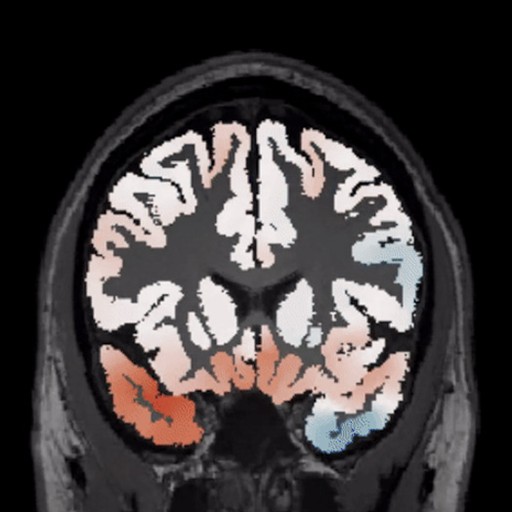

Analysis. Whole-brain morphometric mapping reveals deviation patterns across cortical and subcortical structures

Diagnostics. AI-powered lesion identification combined with expert radiologist validation delivers comprehensive case reports

BrainScores was built exclusively for epilepsy surgery. Generic neuroimaging platforms serve multiple conditions but lack the depth required for focal cortical dysplasia detection.